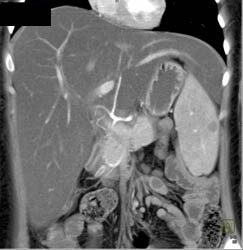

Fatty Liver